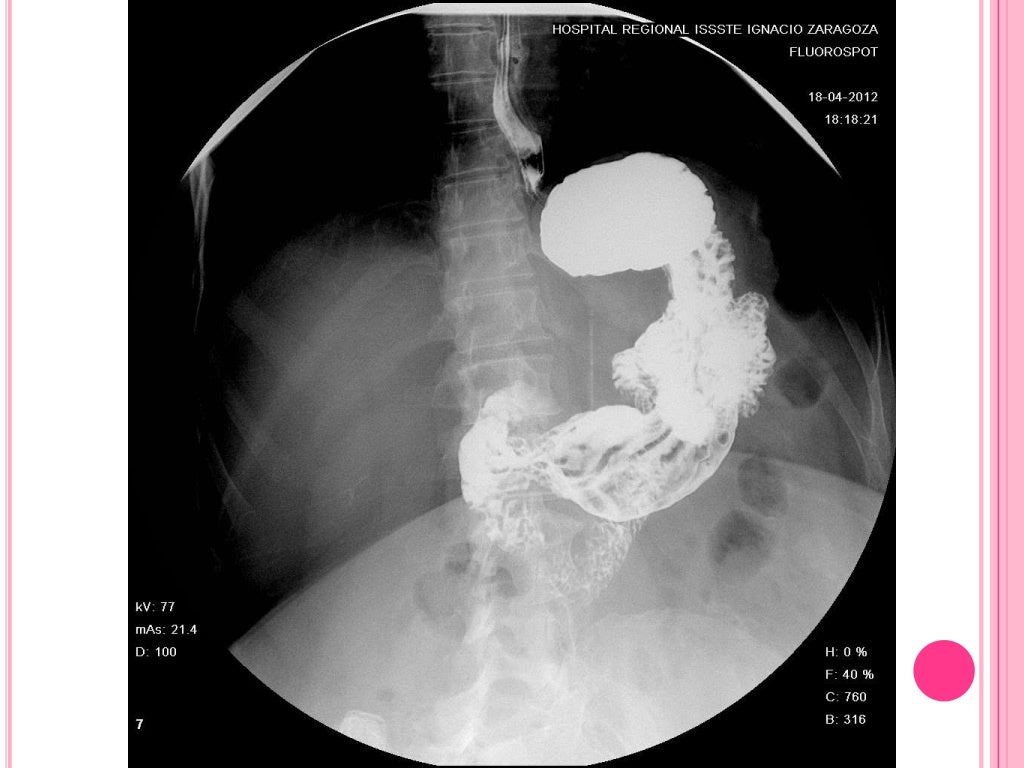

Nos podéis encontrar de lunes a viernes (sábados, domingos y festivos cerrado) en: GEMA Centro Médico de Especialidades I: C/ Nou, 13-15 - Mataró · Horario: de 8:00 a 13:30 y 15:30 a 21:00h GEMA Centro Médico de Especialidades II: C/ Pizarro, 27 - Mataró · Horario: de 8:00 a 20:30h GEMA Rehabilitación y Fisioterapia: C/ José M. Torrijos, 55 - Mataró · Horario: de 08:00 a 20:30h. El tránsito esofagogastroduodenal, conocido en inglés como "upper gastrointestinal (GI) series", usa rayos X para ayudar a diagnosticar problemas del tracto gastrointestinal superior, que comprende el esófago, el estómago y el duodeno. El duodeno es la primera parte del intestino delgado. Estómago. Duodeno.

pruebas radiologicas:Maquetación 1. ESTUDIO ESÓFAGO-GASTRODUODENAL. TRÁNSITO INTESTINAL. ¿QUÉ ES UN ESTUDIO ESÓFAGO-GASTRODUODENAL O UN TRÁNSITO INTESTINAL? El estudio esófago-gastroduodenal es una prueba diagnóstica con contraste que permite obtener imágenes del esófago, el estómago y el intestino delgado.. Cuando la porción del tracto digestivo estudiado corresponde al intestino delgado (duodeno, yeyuno e ileon) hablamos de tránsito intestinal. Cuando la porción del tracto digestivo estudiado corresponde al esófago, estómago y primera porción de intestino delgado hablamos de tránsito esofagogastroduodenal.